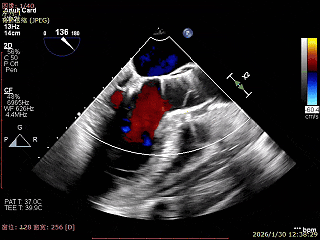

经胸超声报告提示:患者二尖瓣2区及3区前叶关闭时脱入左房,二尖瓣重度反流(MR 4+),患者LA前后径约52mm,LVEDD约68mm,LVESD约42mm,EF值:65%,经胸超声测二尖瓣瓣口面积约6.1cm2,主动脉瓣无冠瓣脱垂并中重度反流,三尖瓣中度反流,估测中度肺动脉高压。

上Color,可见反流主要来自于3区

3区上Color,可见反流来源

LVOT切面可见主瓣二尖瓣术后反流基本消失